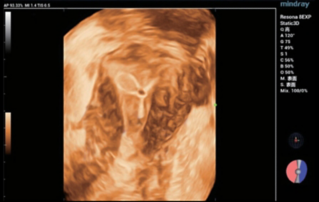

Ultrasound Journal 2 - 분만 후 거근 손상

Female pelvic floor anatomy, which developed since the early 20th century, has had a variety of theories, including integral theory, three levels of vaginal support theory, "hammock hypothesis", and three-chamber system. Supporting structures such as pelvic floor muscles, fascia and ligament play an important role in maintaining the normal function of pelvic floor, among which levator ani muscle group is one of the most important supporting structures.